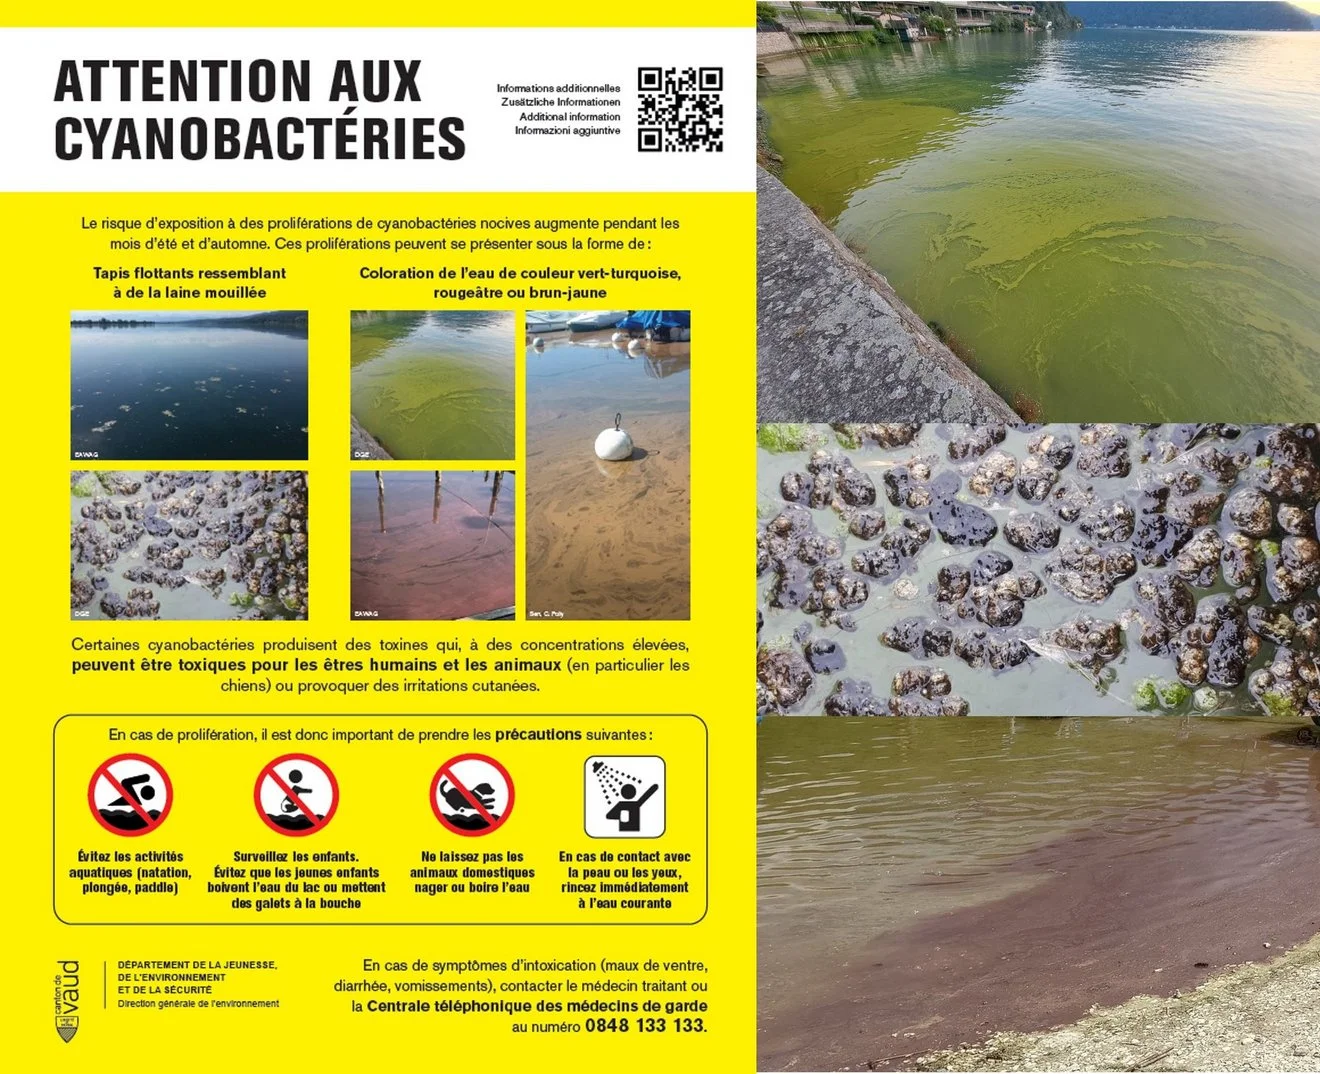

Les Cyanobactéries et les Dangers pour nos Chiens

Age à la stérilisation selon les races

Les Cyanobactéries et les Dangers pour nos Chiens

Age à la stérilisation selon les races